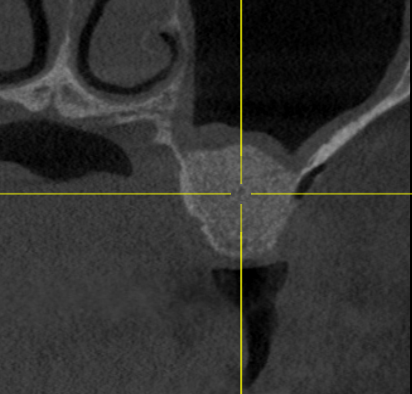

Пациент обратился с целью протезирования. На компьютерной томографии выявлен недостаток костной ткани по высоте (3−5 мм) за счет углубления гайморовой пазухи. Следующим этапом в области отсутствующих зубов 1.5, 1.6 и 1.7 планируется дентальная имплантация.

Врачом А.Г. Геворкяном выполнена операция по наращиванию костной ткани (открытый синуслифтинг). На контрольном снимке определяется увеличение объема костной ткани по высоте.